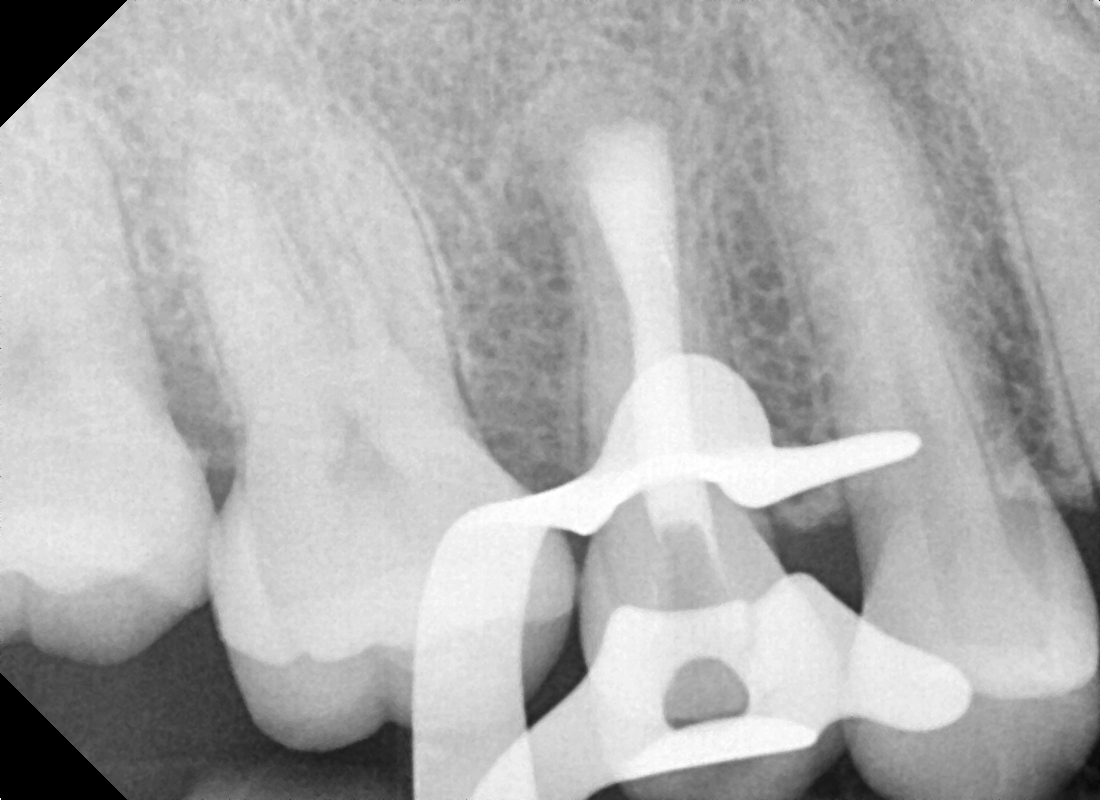

Root canal treatment is a vital procedure designed to save a severely infected or damaged tooth instead of extracting it. When the pulp inside your tooth (containing nerves and blood vessels) becomes inflamed or infected, it can cause severe pain and discomfort. During a root canal, the infected pulp is carefully removed, the inside of the tooth is cleaned and disinfected, and then filled and sealed. This precise root canal procedure allows you to retain your natural tooth, preventing further complications. At True Dental Co, we focus on precise, pain-free root canal treatment to ensure your comfort and preserve your tooth.